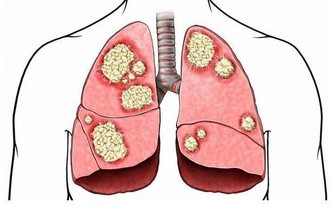

肝癌的產生是肝臟長期、反复徘徊於修復和損傷之間,直到修復跟不上損傷就會發生腫瘤,一旦發生後果嚴重,所以一定要早預防、早發現、早治療。

1、肝癌早期有隱秘性,關注7個症狀

- 胸悶咳嗽

- 肝區疼痛